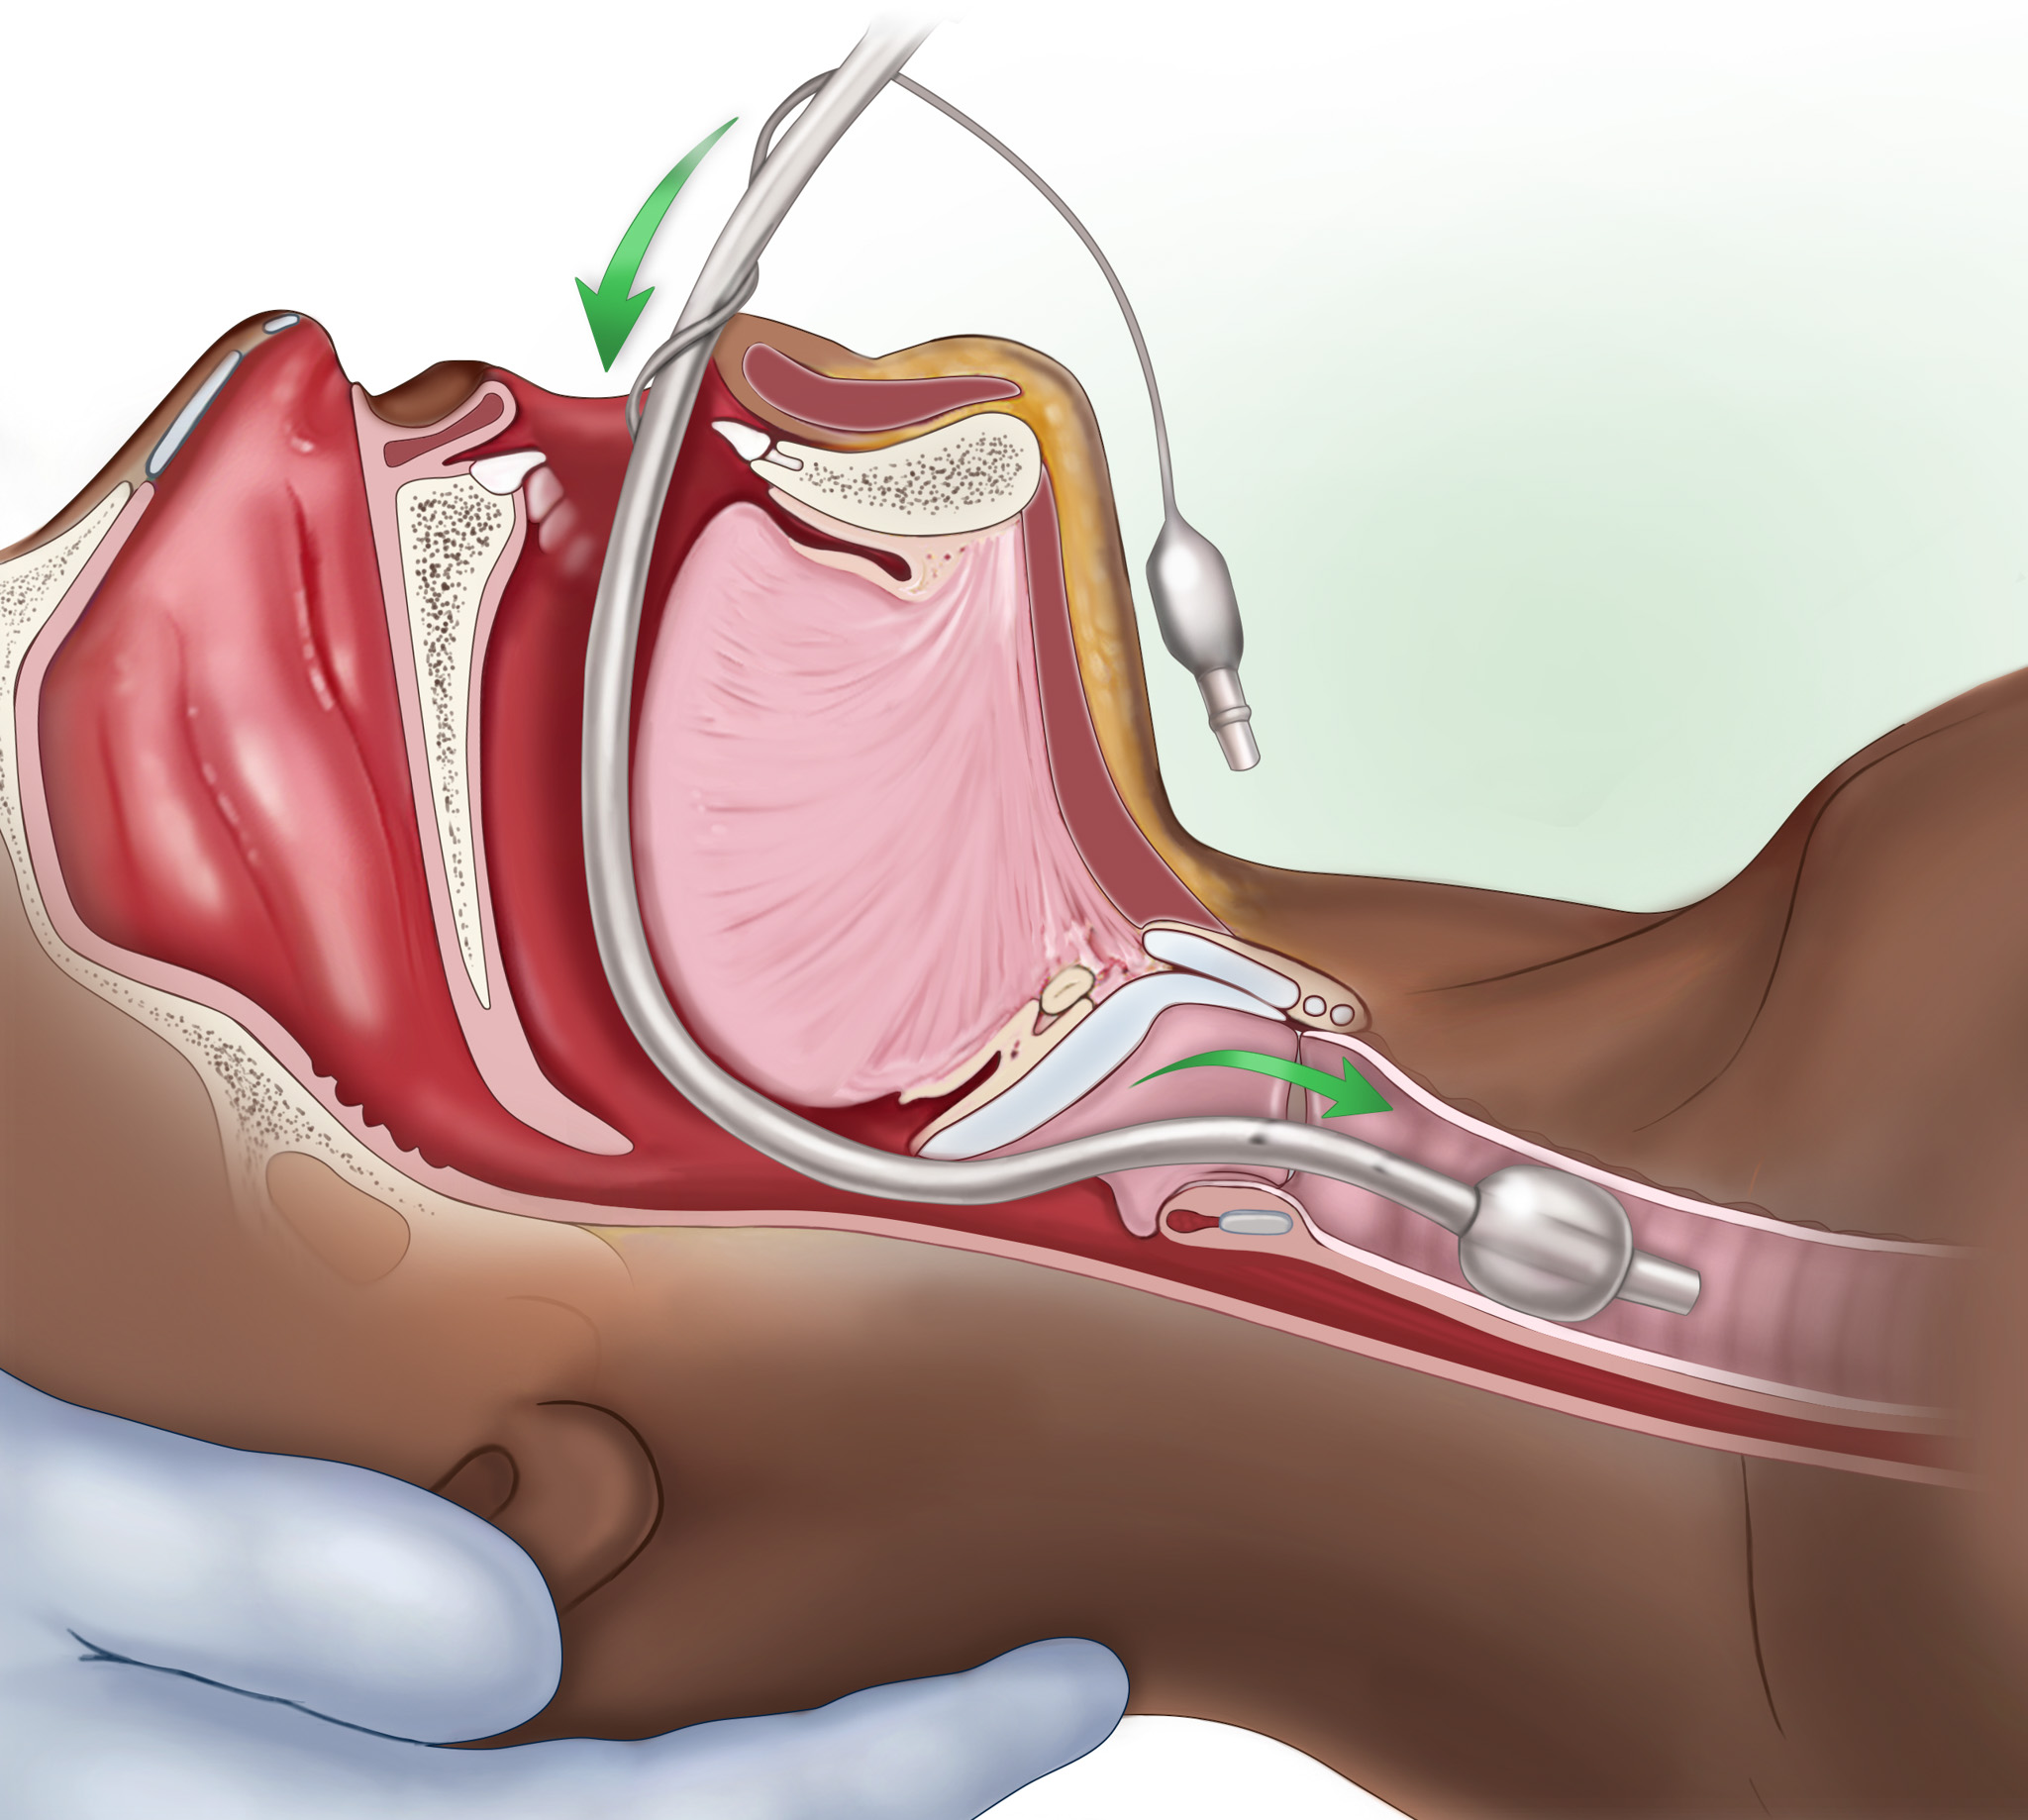

I am a medical illustrator! I wanted to be a doctor and was enrolled in premed, then received a few flyers for colleges in the mail for medical illustration. I decided to change my major from premed to medical illustration. I studied at two private colleges in a combined program for art and medicine.

I create medical illustrations, animations, interactive projects and timelines for physicians, attorneys, medical device and pharmaceutical companies to create illustrations for educational purposes.

I work a lot with attorneys to create medical demonstrative aids for insurance adjusters, mediations and trials. These medical demonstratives help to secure settlements for severely injured and families of decedents.

I am proud to educate people. To scientifically visualize what’s unseen by the naked eye for the general public!

Image Credits

Lindsay Coulter